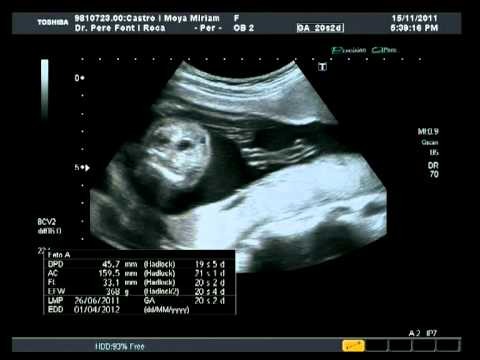

Con respecto a los vídeos, el que podéis ver arriba es de ayer mismo. Viene tal y como nos lo grabó el ginecólogo, así que dura “solo” 7 minutos y al final podéis ver hasta cómo se apaga el ecógrafo (“sorry”). El que os dejo a continuación es el de hace un mes, cuando Miriam supo que era un niño.

Hace cosa de un mes Miriam fue a hacerse una ecografía mientras yo llevaba al mayor al dentista. Ella vio claro que era un niño, el ginecólogo no se pronunció demasiado y yo, cuando vi el vídeo, tampoco fui capaz de mojarme (o mejor dicho, no quise mojarme).